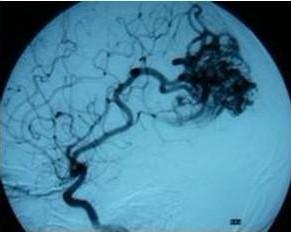

相关图片